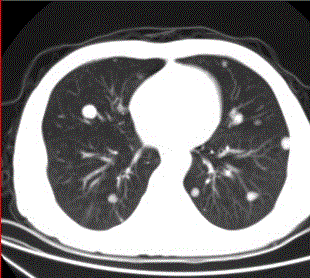

问题 患者男,45岁,因肝硬化、肝癌行肝移植术后6个月,咳嗽2周,来院复查。CR及CT影像如下图。 对于该病例,首选诊断为

选项 A.肺结核 B.肺转移瘤 C.肉芽肿性疾病 D.支气管肺泡癌 E.淋巴瘤 F.支气管肺癌

答案 B